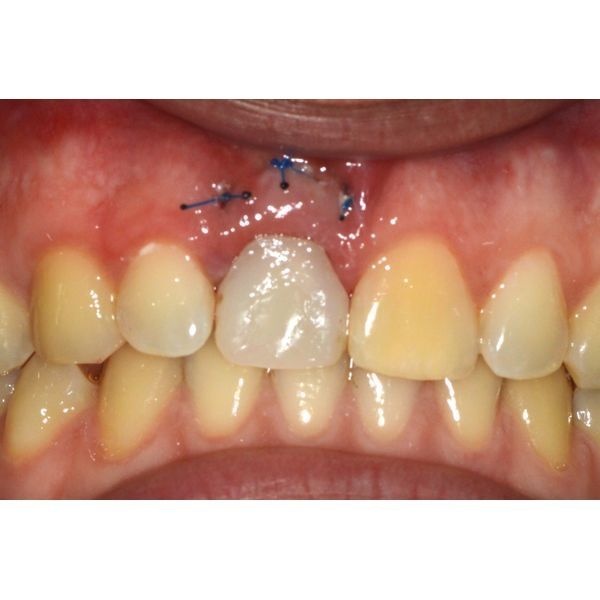

Под местной анестезией удалили зуб, после чего сформировали ложе для имплантата и провели пластику мягких тканей вокруг него. Изготовили и установили временную коронку на 4 месяца.